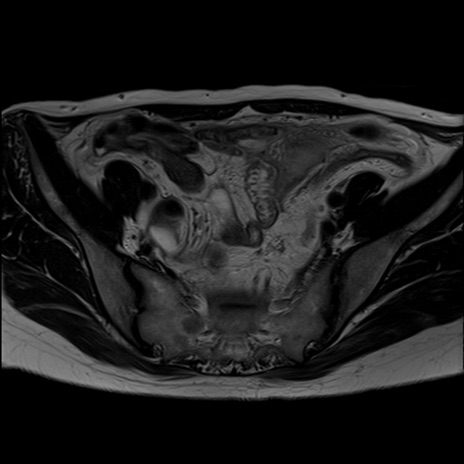

症例39 T2WI(横断像)

MRI(4日後)